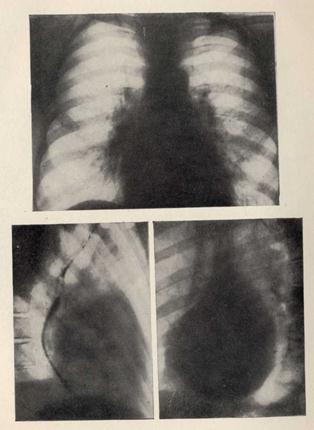

РЕНТГЕНОГРАММЫ БОЛЬНОГО СО СТЕНОЗОМ МИТРАЛЬНОГО ОТВЕРСТИЯ.

Выраженная артериальная гипертензия; отклонение пищевода при его контрастировании по дуге малого радиуса (первое косое положение) и значительное увеличение правого желудочка (первое — второе косые положения).